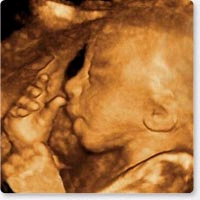

Faszination Live 3D/4D zurück zu Home

Live 3D/4D

paradiesisch schön hier: 3D/4D live in der 30. SSW: